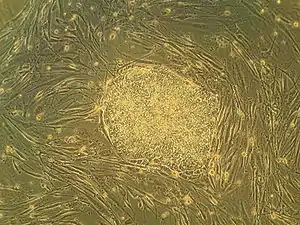

Human embryonic stem cells in cell culture

Embryonic stem cells (ESCs) are pluripotent stem cells derived from the inner cell mass of a blastocyst, an early-stage pre-implantation embryo.[1][2] Human embryos reach the blastocyst stage 4–5 days post fertilization, at which time they consist of 50–150 cells. Isolating the inner cell mass (embryoblast) using immunosurgery results in destruction of the blastocyst, a process which raises ethical issues, including whether or not embryos at the pre-implantation stage have the same moral considerations as embryos in the post-implantation stage of development.[3][4]